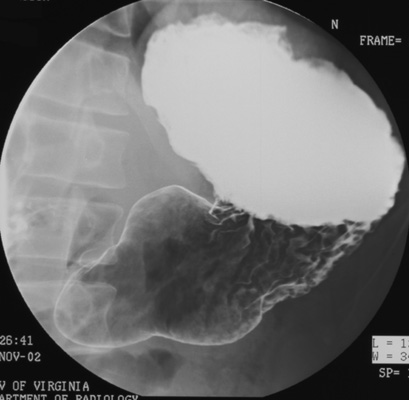

- Gastric body, superior portion (patient RPO). (Elevate

head of table 15 degrees to keep barium from flowing back into gastric fundus as

he rolls back into RPO position.)